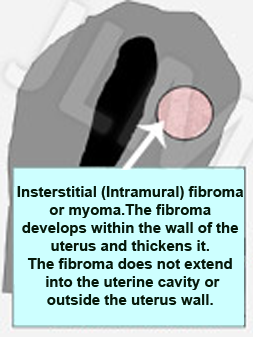

When fibromas grow inside the uterine wall (between the uterine cavity and the outside of the uterus) they are terms interstitial fibromas. This is considered as an intermediate situation and does not always exhibit any symptoms. These fibromas are not a problem as such but they can require attention when they become large and voluminous and when they risk inhibiting fertility (especially as regards IVF (in vitro fertilisation) treatments).

When fibromas grow inside the uterine wall (between the uterine cavity and the outside of the uterus) they are terms interstitial fibromas. This is considered as an intermediate situation and does not always exhibit any symptoms. These fibromas are not a problem as such but they can require attention when they become large and voluminous and when they risk inhibiting fertility (especially as regards IVF (in vitro fertilisation) treatments).